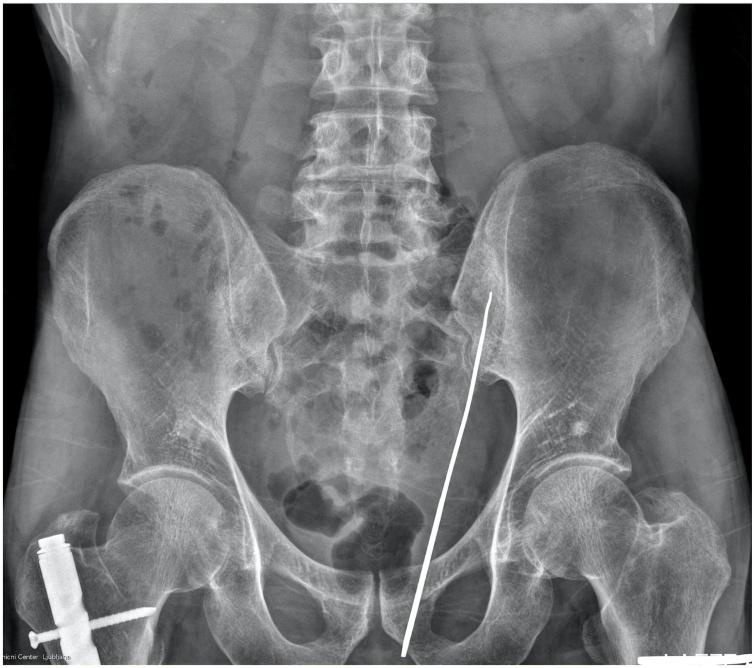

In this article the authors present a case report of a 63-year old man with an impalement injury in the left gluteus, who was managed conservatively.

在本文中,作者呈现了一例63岁男性左臀穿刺伤的病例报告,该患者接受了保守治疗。